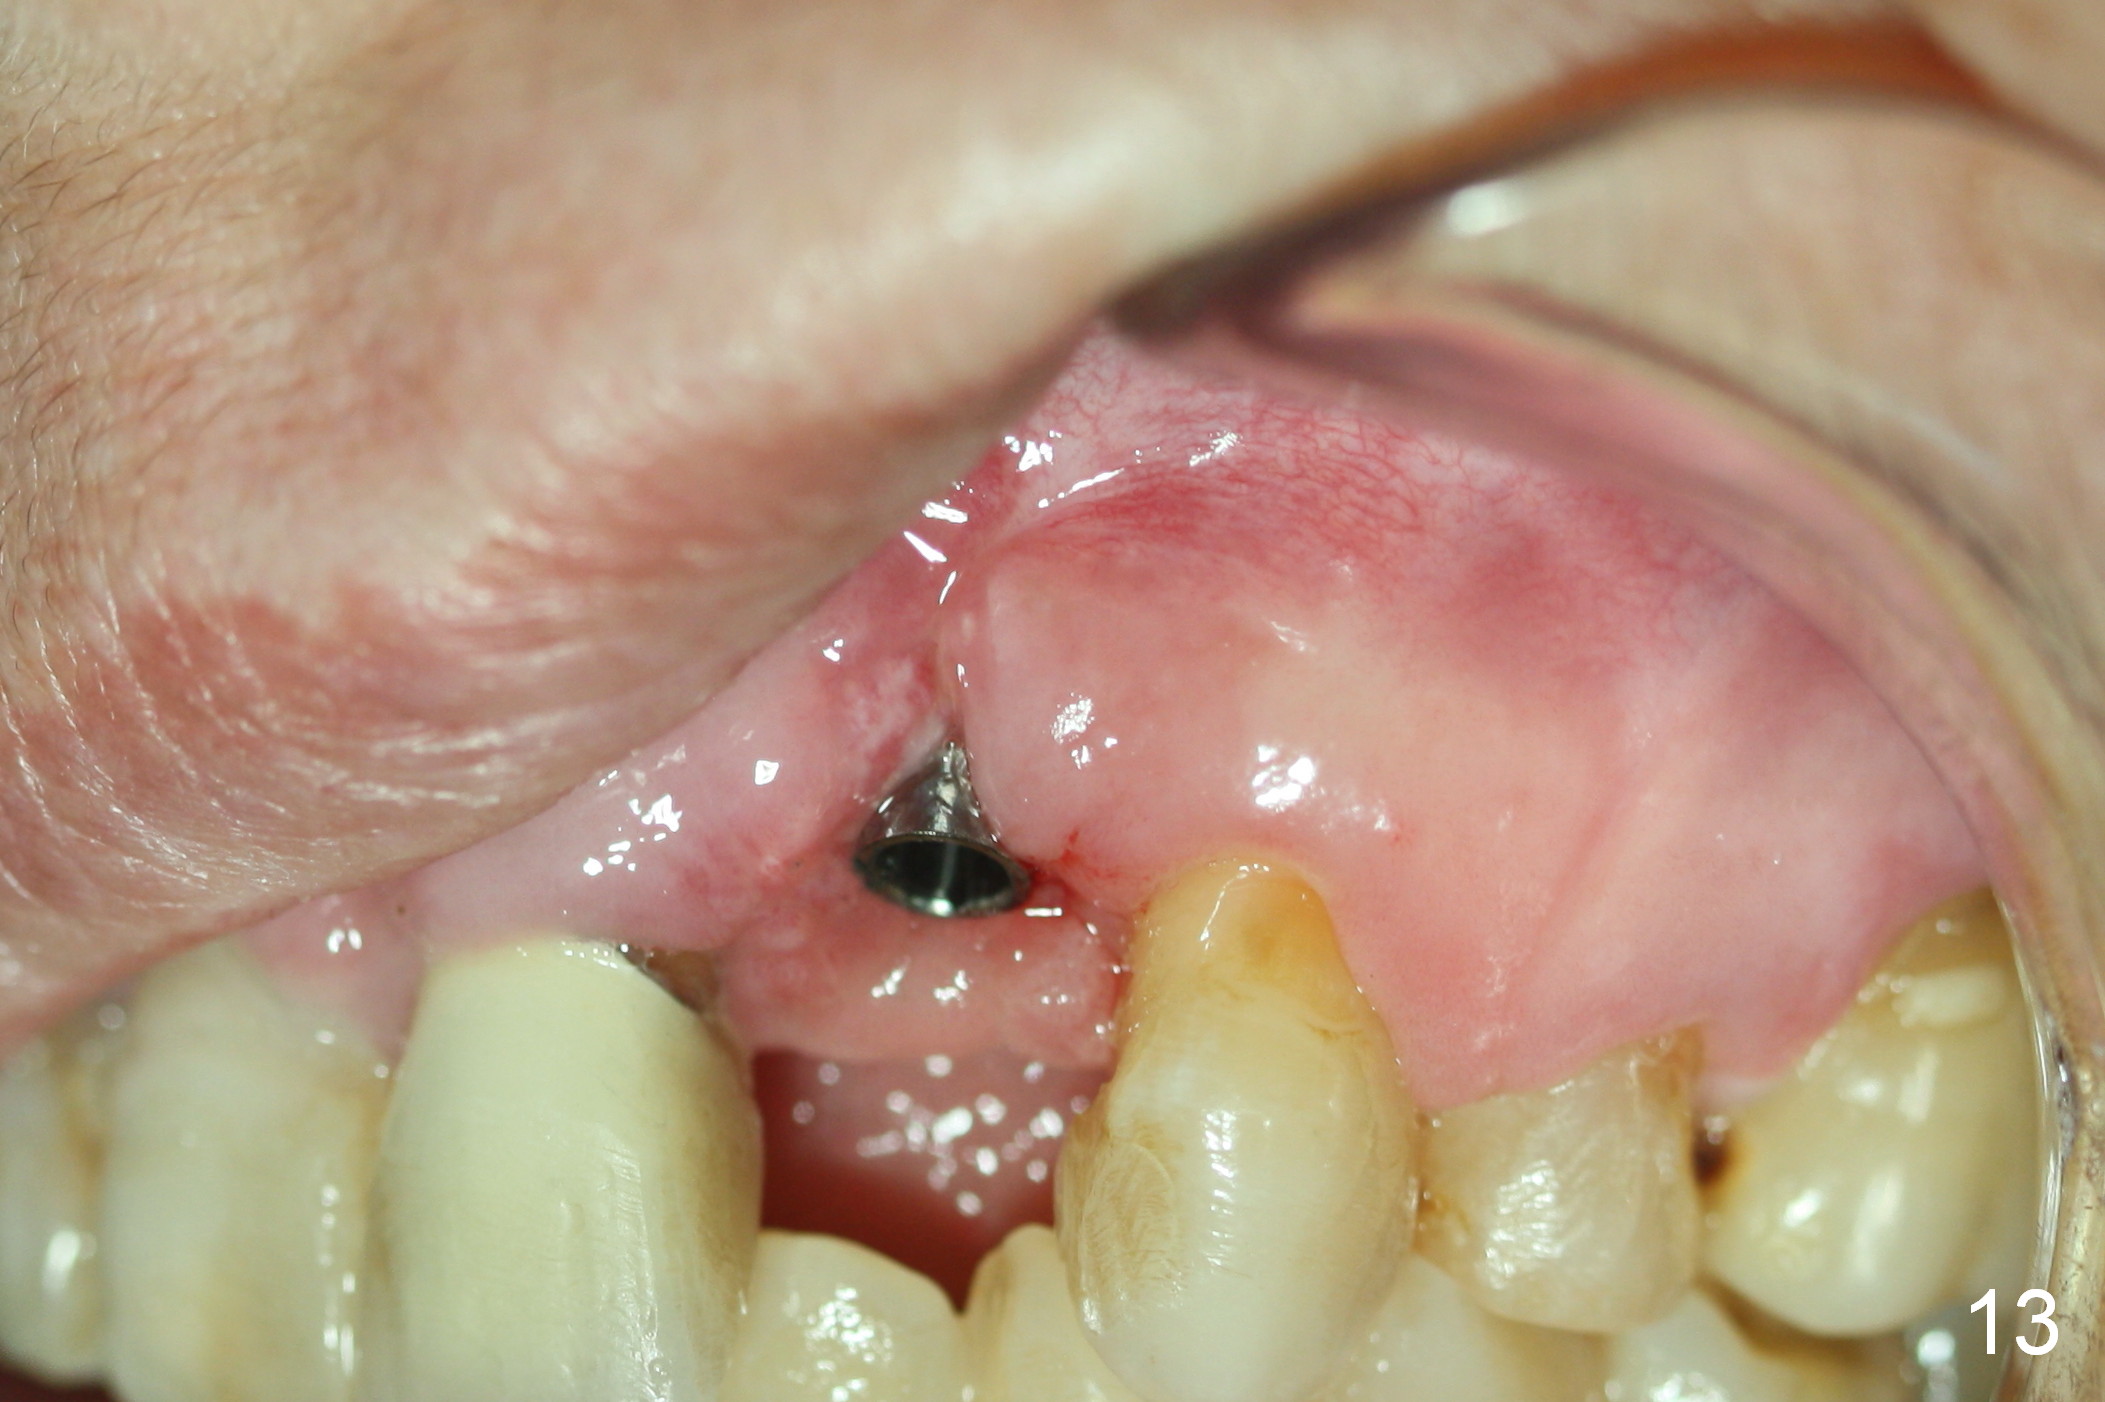

As expected, there is midbuccal tissue deficiency (Fig.9,10: 2 months postop). After discussion, a free gingival graft from the palate is placed (Fig.11,12 *). Two weeks later, the graft sloughs (Fig.13). A pedicled flap is designed (Fig.14) and transferred to repair the defect (Fig.15,16).